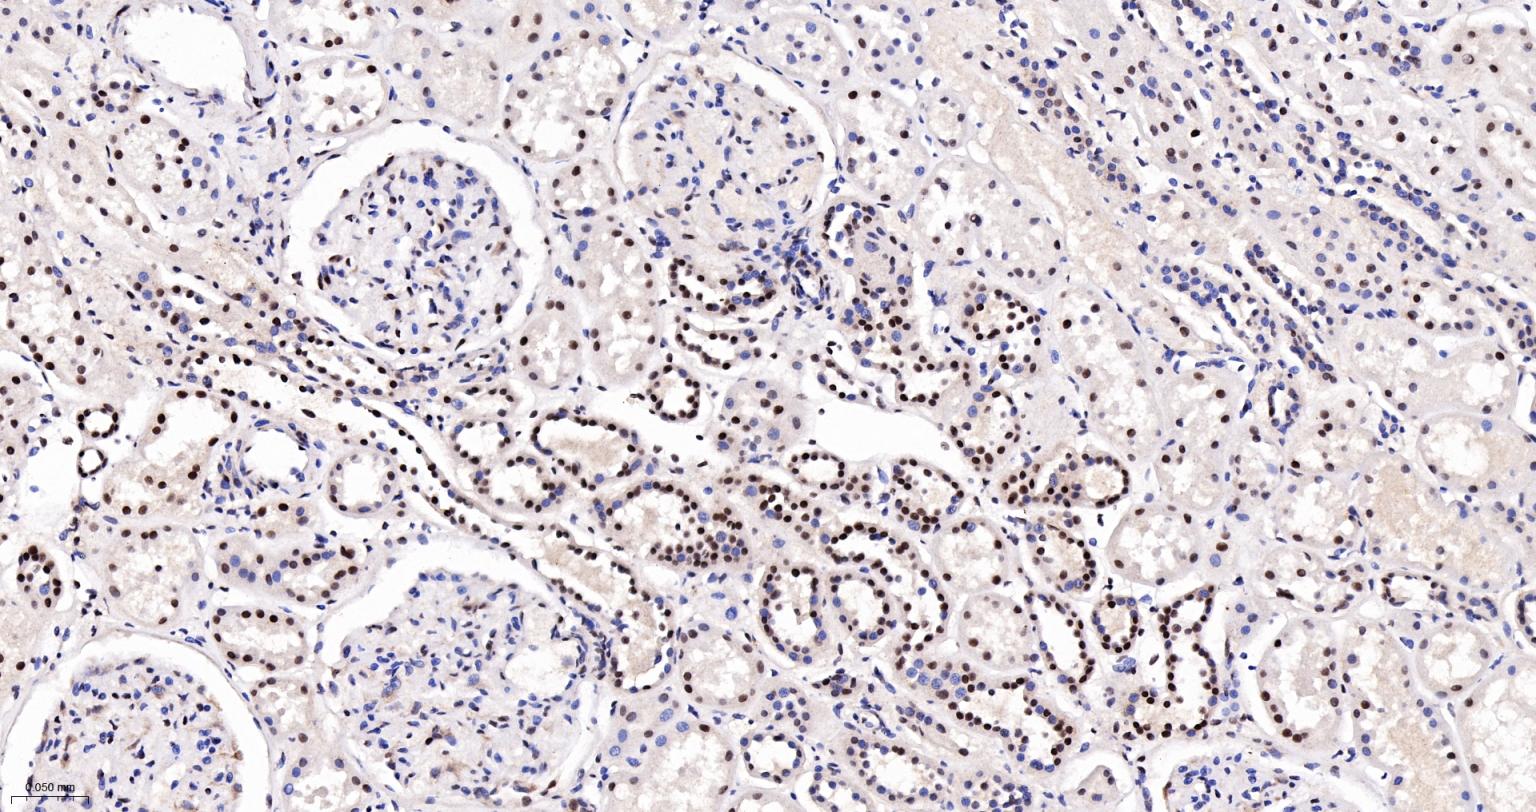

Paraformaldehyde-fixed, paraffin embedded Human Kidney; Antigen retrieval by boiling in sodium citrate buffer (pH6.0) for 15 min; The section was incubated with CDC5L Monoclonal Antibody, Unconjugated (bsm-61335R) at 1:200 overnight at 4°C, followed by conjugation to the bs-0295G-HRP and DAB (C-0010) staining.